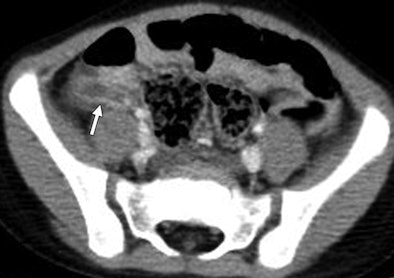

| CT scan through pelvis of 4-year-old girl. Radiologist at outside referring institution initially interpreted study as "normal," whereas specialty radiologist at tertiary care hospital recognized distended appendix (arrow) with increased enhancement, periappendiceal inflammation, and small fecalith. |